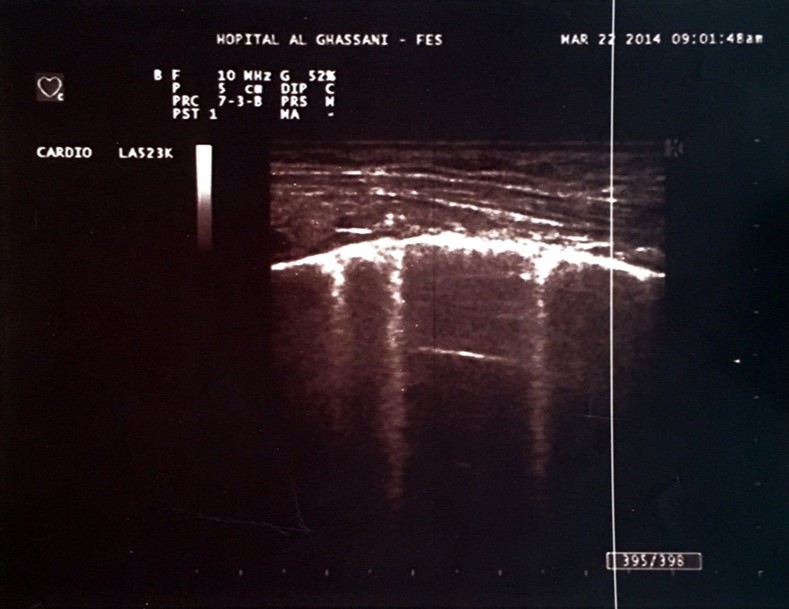

One of the most interesting tools is the use of the lung ultrasound to detect the presence of extravascular lung water (LW). In the presence of excessive LW, the US beam is reflected by subpleural thickened interlobular septa, a low impedance structure surrounded by air with a high acoustic mismatch. This US reflection generates hyperechoic reverberation artifacts between thickened septa and the overlying pleura that are known as “lung comets” or B-Lines 5. Lung comets are defined as vertical artifacts arising from the pleural line and extending to the edge of the screen that move synchronously with respiratory acts 6 (Figure 1).

Figure 1.Hyperechoic microreflections indicating the presence of extravascular lung water known as B-lines in one of our patients.